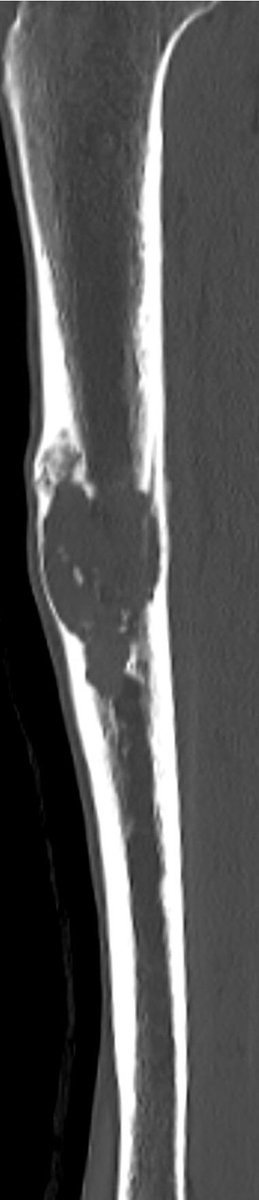

A single destructive lesion or multifocal tumour,may be identified, affecting cortex and often extending to the medulla,most commonly in the mid-tibial shaft.The lesion is typically eccentric and may cause mild bone expansion,endosteal scalloping and eventually destroy the cortex

AD typically appears multilocular and trabeculated, with intervening and surrounding sclerosis. A distinct periosteal reaction is unusual. An extra-osseous mass and pathological fracture may be seen

The tumour in the current case appeared to have arisen in the anterior cortex, extending inferiorly into both cortex and medulla, as a single focus of disease. The trabeculated appearance on radiographs appears to reflect the unusual extension of tumour through tibial cortex.

, with preservation of vertical ridges of cortical bone, surrounded by tumour, adjacent to areas of marked cortical thinning. Oedema-like hyperintensity on the bone surface suggests imminent fracture